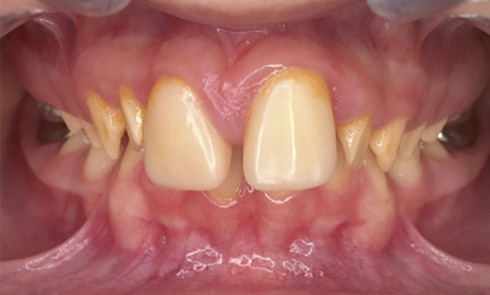

Amélogenèse imparfaite

L’amélogenèse imparfaite (AI) est l’expression d’altérations génétiques associées à des mutations de nombreux gènes codant pour les protéines de l’émail...

Article réservé à nos abonnés Amélogenèse imparfaite prise en charge de l’enfance à l’âge adulte

L’amélogenèse imparfaite, nom donné à un groupe hétérogène de pathologies affectant le développement de l’émail des deux dentures, a pour...

Définition L’amélogenèse imparfaite est le nom donné à un groupe hétérogène de pathologies caractérisées par un défaut inné du développement...

Article réservé à nos abonnés Approche moderne de la réhabilitation prothétique fixée des amélogenèses et dentinogenèses imparfaites de l’enfance à l’adolescence

La réhabilitation prothétique fixée des amélogenèses (AI) et des dentinogenèses imparfaites (DI) constitue un véritable challenge pour le praticien, comme...